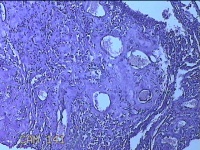

子宫腔妊娠残留物

早期人工流产术后 疤痕子宫 不全流产?

停经11周。

灰白暗红色不规则碎组织4x3.5x0.8cm一堆,未发现明显的绒毛样组织。